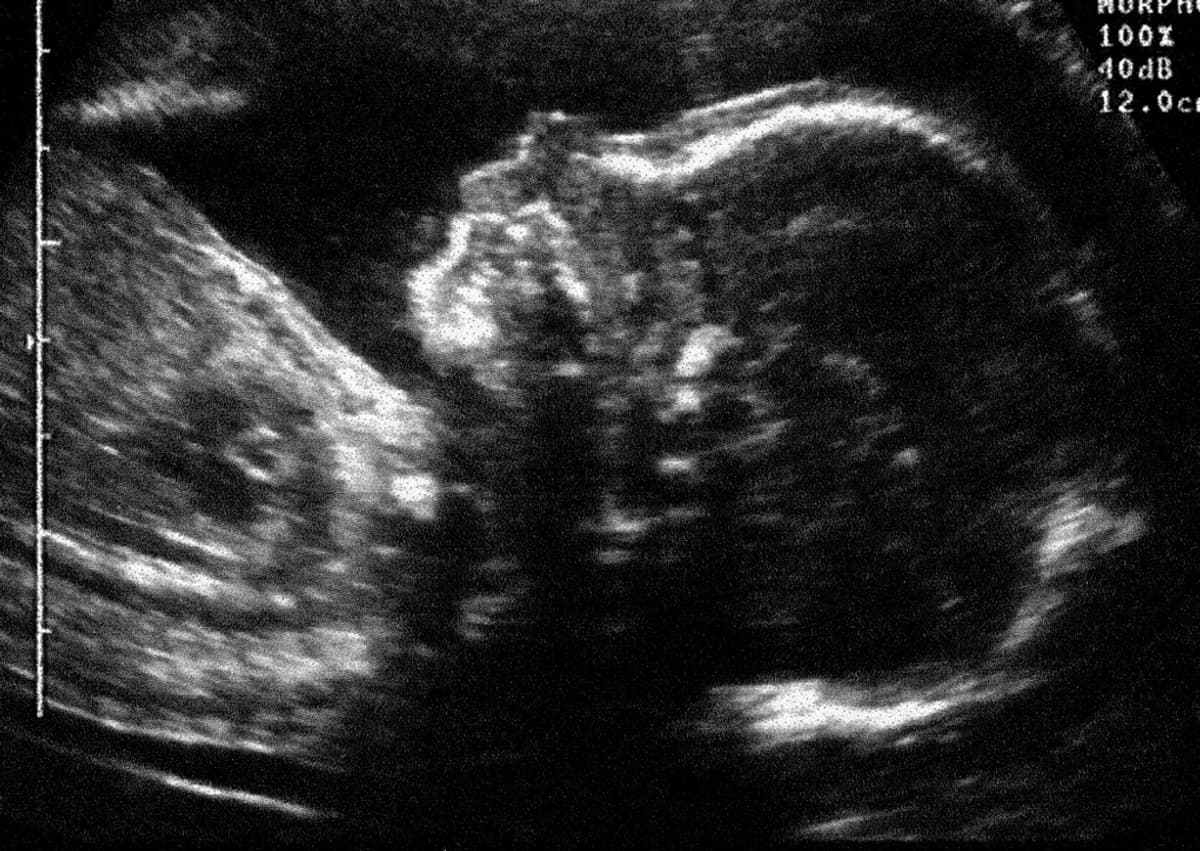

Il s'agit de tests commercialisés par le groupe finlandais PerkinElmer et qui visent à dépister les risques de trisomie 21 chez le foetus lors du premier et du deuxième trimestre de grossesse. Cette annonce intervient dans un contexte où des pénuries frappent de plus en plus de médicaments en France comme à l'international.